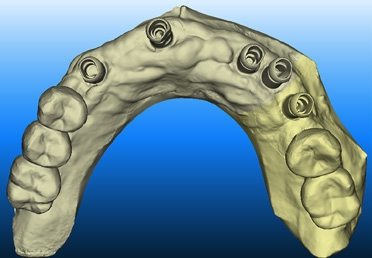

Die Implantatprothetik ist einer der Bereiche, in dem die digitale Abformung eine große Erleichterung für den Zahnarzt darstellt. Die Übertragung der Implantatsituation im Mund war bisher für Patienten und Arzt mit konventionellen Methoden unkomfortabel und schwierig. Durch lange Übertragungspfosten war gerade im Molarenbereich das Entfernen der Abformung häufig schwierig. Zudem war die gleichzeitige Abformung von Implantaten und Zähnen durch Materialverziehungen oft nicht in allen Bereichen präzise, sodass Wiederholungen der Abformung nötig wurden. Diese Problematiken liegen bei der digitalen Abformung nicht vor. Je nach System wird zunächst der Restkiefer inklusive der offenen Implantatschraube gescannt, um das Emergenzprofil darzustellen. Die Übermittlung des Emergenzprofils ist eine Information, die zuvor dem Labor nicht zur Verfügung stand und funktionell wie ästhetisch hochwertigere Ergebnisse ermöglicht. Anschließend wird ein zu Implantatsystem und Implantatgröße passender Scanpfosten eingeschraubt, um die Implantatposition zu übertragen. Dieser wird ebenfalls gescannt. Die Software des Scanners rechnet diesen automatisch in den ersten Scan ein. Nach Abformung des Gegenkiefers und der digitalen Bissnahme ist der Vorgang der Abformung beendet und die Daten können ins Labor versandt werden. Sollten weitere präparierte Zähne in dieser Abformung enthalten sein, können diese natürlich einzeln präzise abgeformt und sofort im Monitor überprüft werden. Auf weitere gnathologische Vermessungen gehen wir hier nicht ein, diese sind aber natürlich analog wie digital möglich.

Für den weiteren Workflow im Labor gibt es je nach Implantatsystem und Anbieter verschiedene Möglichkeiten. Eine Vorgehensweise ist, dass ein physisches Modell gedruckt wird, in das ein Modellimplantat – ähnlich eines Laboranaloges – eingeschraubt oder geklebt werden kann. Die hierfür nötige Aussparung wird auf Basis der Scandaten und des Scanbodys zuvor berechnet. Im weiteren Prozess wird ein individuelles Abutment oder eine verschraubte Krone generiert und gefertigt. Der Datensatz eines Abutments kann in die Konstruktionssoftware eingerechnet werden, und darauf kann der geplante Zahnersatz gefertigt werden. Einen anderen Weg geht hier die Firma Dentsply Sirona über ihre Atlantis-Plattform. Hier werden die Daten der Abformung in deren Portal hochgeladen. Dort wird dann ein Konstruktionsvorschlag für das Abutment erstellt, der in jeder Dimension vom Zahntechniker bearbeitet werden kann. Nach Bestätigung des Abutmentdesigns wird dieses von der Firma gefertigt und dem Labor zugeschickt. Zeitgleich erhält das Labor für die weitere Herstellung des Zahnersatzes einen Datensatz (core-file), in dem das Abutment als Stumpf eingerechnet ist. Es besteht hier nicht die Möglichkeit, Abutment und Zahnersatz zusammen in einem Modell zu kontrollieren. Beide Techniken funktionieren problemlos und sind für den Praktiker bei höherer Präzision eine enorme Arbeitserleichterung.